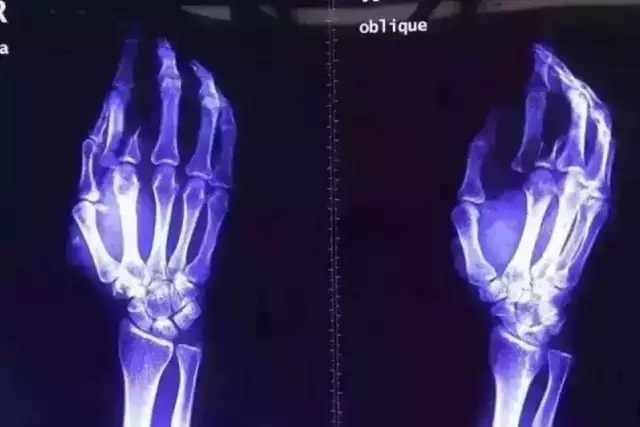

又一起傷醫(yī)事件刺痛了我的眼球,看著觸目驚心的血腥圖片,一股寒涼之氣瞬間侵入心靈,攪動著悲憤的心情。

親眼看到肇事方在醫(yī)生辦公室拍敲桌子,惡言相向,原因是不滿醫(yī)生的診療方式,認(rèn)為過度檢查。要知道,CT檢查對顱腦外傷尤為重要。那時,他又能否站在醫(yī)生的角度,站在尊重生命的角度,收斂自己的脾氣和自私的想法?